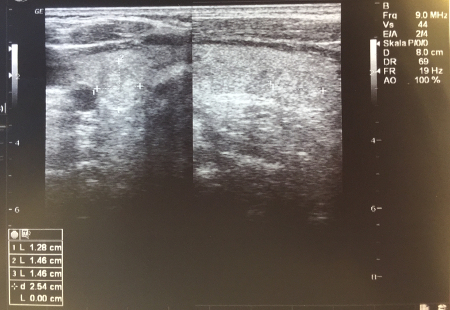

[Figure caption and citation for the preceding image starts]: Ultrasound image of thyroid noduleCourtesy of Getty images; used with permission [Citation ends].